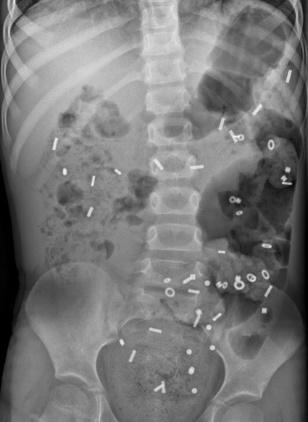

- Röntgenfoto van de buik: Hiermee kan worden bekeken hoe ernstig de verstopping is. Soms wordt dit gecombineerd met een markerstudie, waarbij uw kind capsules inneemt om de snelheid van de ontlasting te meten.

Coloninloop: Dit is een onderzoek waarbij contrastvloeistof via het poepgat wordt ingebracht om de dikke darm beter te bekijken. Daarna worden er een aantal röntgenfoto's na elkaar gemaakt, zodat de darm goed te zien is. Zo kan de arts goed beoordelen of de darm lang, wijd of kronkelig is.- Als uw kind dit spannend vindt, kan een medisch pedagogisch zorgverlener u en uw kind helpen om ervoor te zorgen dat dit proces zo soepel mogelijk verloopt.

- Coloninloop: Onderzoek waarin de dikke darm zichtbaar wordt gemaakt met vloeistof en rontgenfoto’s.